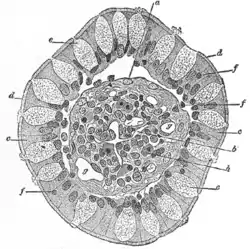

Vertical section of a villus from the dog's small intestine. X 80. (Simple columnar epithelium labelled at right, third from the top.)

Vertical section of a villus from the dog's small intestine. X 80. (Simple columnar epithelium labelled at right, third from the top.) Transverse section of a villus, from the human intestine. X 350.

Transverse section of a villus, from the human intestine. X 350.

a. Basement membrane, here somewhat shrunken away from the epithelium.

b. Lacteal.

c. Columnar epithelium.

d. Its striated border.

e. Goblet cells.

f. Leucocytes in epithelium.

f’. Leucocytes below epithelium.

g. Blood vessels.

h. Muscle cells cut across.